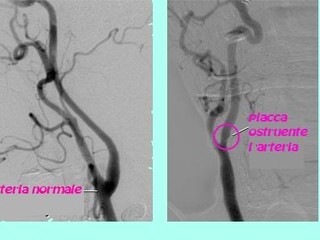

• la formazione di coaguli di sangue in una delle arterie molto piccole del cervello (trombosi). Questo è di solito preceduto da un restringimento graduale dei vasi sanguigni causato da un accumulo di grassi chiamato Aterosclerosi (ateromi = depositi di colesterolo e di tessuto adiposo sclerosi + restringimento) . il restringimento delle arterie del cervello è lo stesso il restringimento che si verifica nelle arterie del cuore che precedono un attacco di cuore.

• ecografia carotidea è un test per cercare restringimento dei vasi sanguigni nella parte anteriore del collo che forniscono il maggior apporto di sangue al cervello.